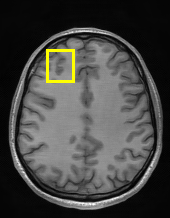

Edge preserving has always been a crucial concern in the design of reconstruction models. To improve the quality of reconstructed images and preserve image edges, some works suggested introducing edge priors in the original restoration problem to preserve image edges [4, 34]. However, they will suffer from complicated algorithm design and time-consuming training processes. Recently, some more efficient methods have been proposed to use edge maps as external guidance for image restoration. For example, Yang et al. [48] used off-the-shelf edge detectors to extract image edges from the degraded images. Fang et al. [12] predicted image edges by constructing an edge reconstruction network. Huang et al. [18] designed a novel dual discriminator GAN framework for solving fast multi-channel MRI, in which one GAN network is built for edge information enhancement. Inspired by these methods, we also consider introducing image edge prior as external guidance to MRI reconstruction since 1) image edges are prominent and distinguishable features in MRI (see Fig. 1), which can serve as a good guide to the model to recover high-frequency details; 2) the ground truth edges can be easily fetched via ordinary edge extraction operators, like Canny, Sobel, and Prewitt, which means that the edge maps can be learned in a data-driven manner. However, how to effectively utilize image edge priors to guide image reconstruction still remains a challenge. In some methods, edge information was simply concatenated with the input image and passed to the next stages. Though this is a simple way to utilize the edge priors, it may not give full play to the guiding role of the edge priors. Therefore, in this work, we want to explore a more efficient and effective mechanism to fully take advantage of image edge priors.

fastMRI is a large-scale MR dataset jointly established by Facebook AI Research and NYU Langone Health. It provides both knee and brain datasets for evaluation. In our work, we use the multi-coil knee dataset, which was acquired on three clinical 3T systems or one clinical 1.5T system using a 15-channel knee coil array. The dataset includes data from two pulse sequences, yielding coronal proton-density weighting with (PDFS) and without (PD) fat suppression. As is shown in Fig. 1, PD images usually contain more structural and prominent edge features than PDFS images, which suggests that it is more challenging to use edge guidance on PDFS datasets. Therefore, we explore the effectiveness of EAMRI on these two modalities. Following [13], for both PD and PDFS knee datasets, we separately filter out 227 volumes (8332 slices) for training and 24 volumes (1665 slices) for testing. The dataset is centrally cropped to .

Moreover, in Fig. 6, we provide a visual comparison of the reconstruction results of these models. We can see that EAMRI has fewer bright spots in the heatmaps, which means less error between the EAMRI reconstructed image and the ground truth image. Meanwhile, according to the zoomed-in images of the selected areas, we can observe that our EAMRI can reconstruct more clean and accurate edges. This further validates the validity of EAMRI. Both the quantitative and the qualitative results for the single-coil MRI reconstruction demonstrate the effectiveness of EAMRI.